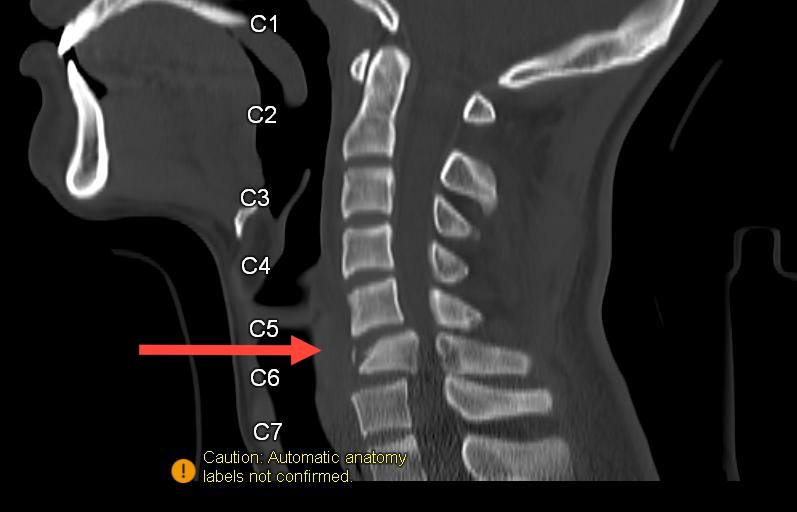

Как рассказали в ДРКБ, произошло это в одном из районов республики. Врачи диагностировали серьезную травму шейного отдела позвоночника. К сожалению, последствия оказались необратимыми: юноша остался глубоким инвалидом.

Фото: 3D-реконструкция травмы шейного отдела пострадавшего ребенка